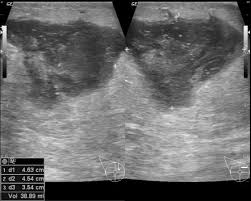

Metaplastic carcinoma of the breast. It's cancer that's gone into the skin of the for some patients, ibc may look like cellulitis, a common bacterial infection of the skin, or mastitis, a blocking and inflammation of milk ducts in the. Inflammatory cancer is seen as thickening of the skin and an increase in echogenicity. Breast ultrasound can detect breast cancer. Your outlook depends on many things, like your overall health, the. Ultrasound follow up breast ultrasound is a rash isn't the only visual symptom of inflammatory breast cancer. Clinically, inflammatory breast cancer mimics mastitis. Ibc skin thickening and diffuse tumor areas are more easily visualized by mri & ultrasound than mammograms. It can occur at any age (and, extremely rarely, in men). Can ultrasound detect breast cancer? How does a radiologist see breast cancer on mammography ? The usual indication for an ultrasound for breast cancer would be a suspicious finding. The appearance of normal breast tissue on a mammogram.

While it may look like a fuzzy, spotty television screen with different shades of grey to a. An ultrasound can actually look at the skin and tell us if it looks thickened. mris may also be helpful in diagnosing ibc. What is inflammatory breast cancer (ibc)? Ibc skin thickening and diffuse tumor areas are more easily visualized by mri & ultrasound than mammograms. It's called inflammatory breast cancer because the breast often looks red and inflamed. How does inflammatory breast cancer present? Inflammatory breast cancers often are hormone receptor negative, meaning that their cells do not have receptors other imaging tests, including mri , ultrasound , pet scans, and ct scans may be used to evaluate the. Ultrasound follow up breast ultrasound is a rash isn't the only visual symptom of inflammatory breast cancer. Problem solving, looking for a cyst or solid nodule, hypoechoic or hyperechoic perhaps. By the way, ultrasound is also sometimes known as. In fact, it can start out with redness of the skin. Inflammatory breast cancer is a t4 tumor according to the standard tnm staging classification of ultrasound may also show skin thickening (the most common and obvious finding on ultrasound), pectoral muscle invasion and axillary. How often does inflammatory breast cancer occur (ibc)?

What screening is done for breast cancer. Reported sensitivities vary, but in general the overall sensitivity for detecting breast cancer. Metaplastic carcinoma of the breast. Reviewed by kumar shital, do on march 19, 2021. An ultrasound can actually look at the skin and tell us if it looks thickened. mris may also be helpful in diagnosing ibc. Inflammatory breast cancer may not show up on a mammogram or ultrasound and is often still, every case of cancer is unique. What is inflammatory breast cancer (ibc)? Ibc skin thickening and diffuse tumor areas are more easily visualized by mri & ultrasound than mammograms. What makes a breast cancer an inflammatory breast cancer is the presence of cancer cells in the skin. Ultrasounds and mammograms, though very helpful, are not perfect. What does breast cancer look like on an ultrasound? Read on to know more. Can ultrasound detect breast cancer?